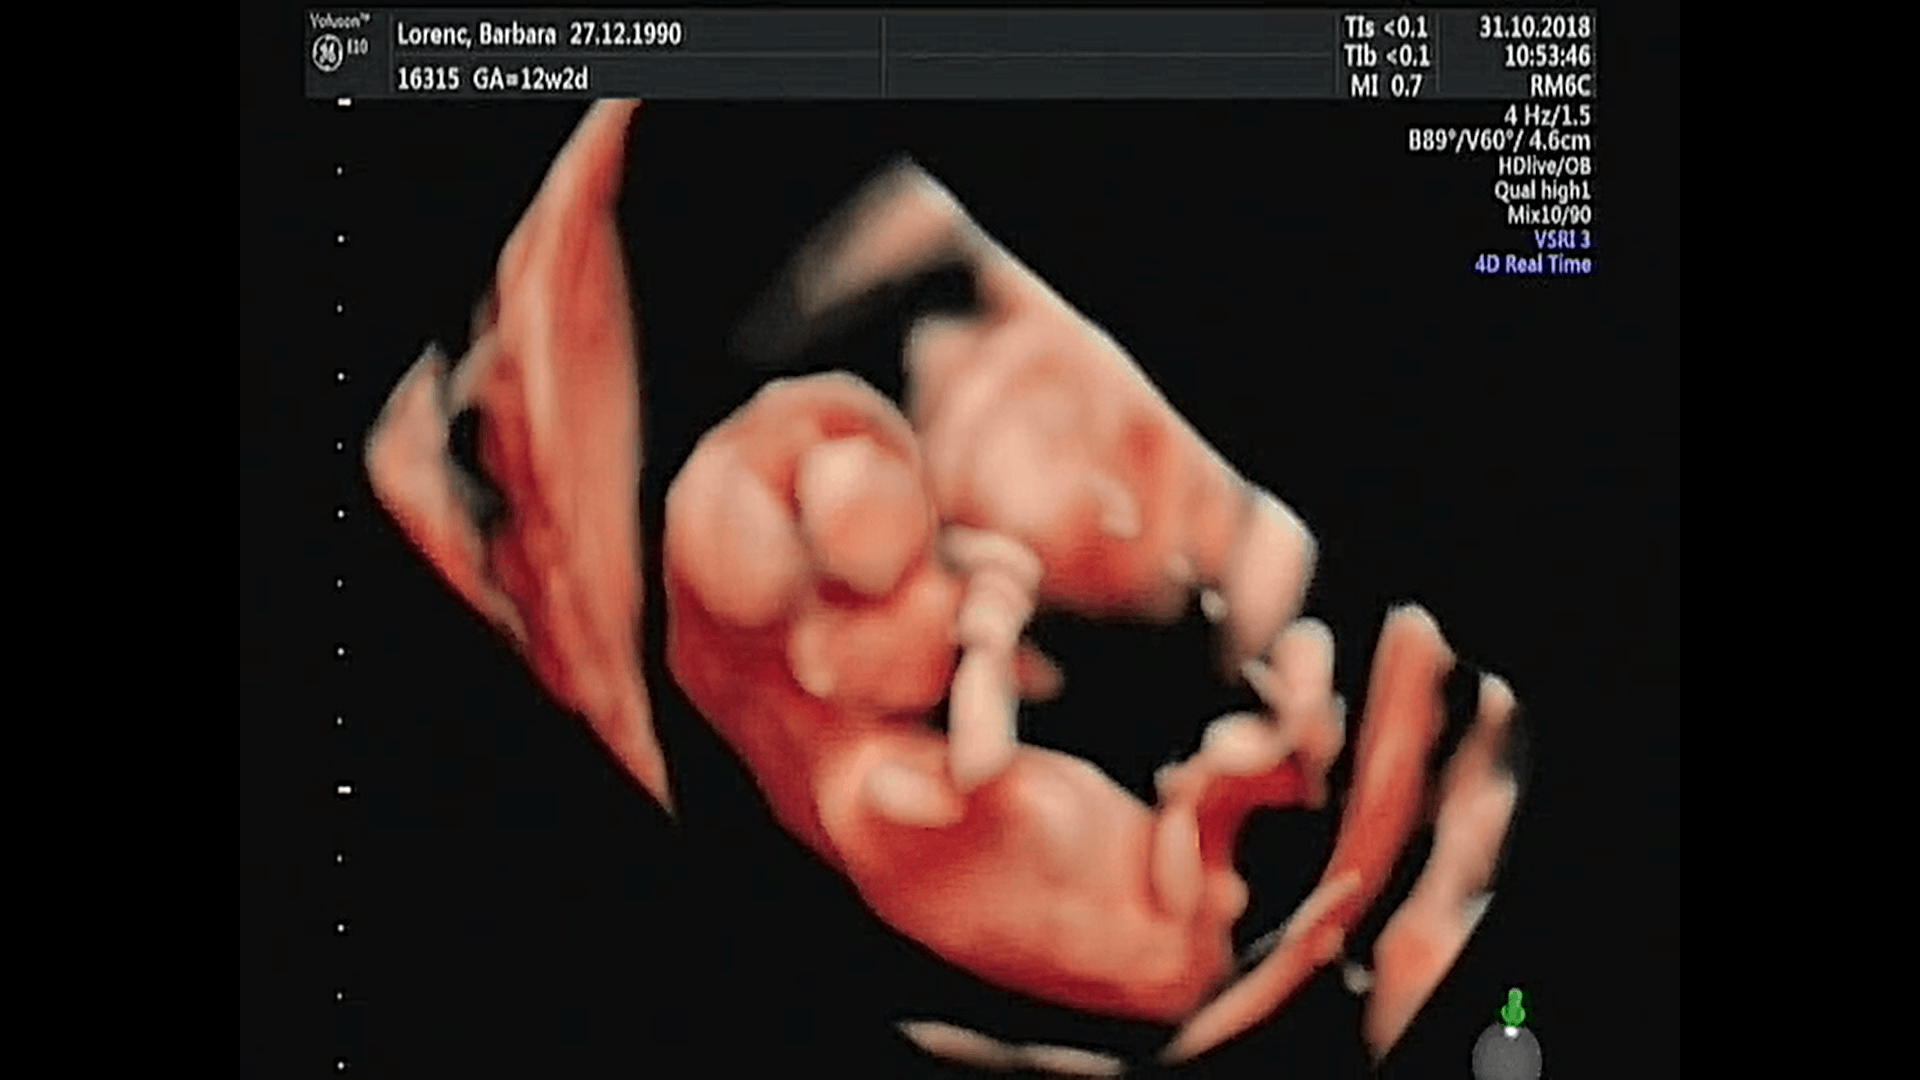

Witam w 19 tygodniu ciąży dowiedziałam się ze będę miała dziewczynkę w 20 tyg okazało się jednak , że to chłopak. Sama już nie wiem bo na jednym usg widać na pewno dziewuche a na drugim chłopca. Może to pempowina ?? Może ktoś mi pomoże rozwiązać ta zagadkę